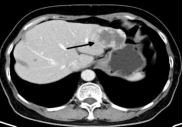

患者李先生(化名),因上腹部不适来我院就诊。经过彩超、腹部增强CT等详细检查,发现肝左叶有两枚血管瘤。较大一枚位于肝脏边缘包膜下且体积较大,瘤体直径将近6cm ,一旦发生破裂,后果不堪设想。

经过积极准备,手术在数字减影血管造影(DSA)的引导下进行。在湖北省肿瘤医院放射介入科主任闫卫鹏教授的指导下,我院放射介入科周巍主任主刀。术中发现,供应肝脏血管瘤的肝动脉极其迂曲,但介入团队配合默契,成功将微导管精准引入肝血管瘤的供血动脉。随后,使用栓塞剂对血管瘤进行栓塞,阻断血管瘤的血液供应,使其逐渐萎缩、坏死 。手术过程十分顺利,患者体表仅留下针眼大小微小创口。